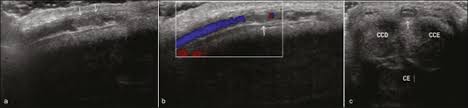

The second good news that you can easily heal it with home based remedies. Pearly Penile Papules or PPP is basically a skin disorder. Symptomatic patients without flow in the color Doppler US after the sixth week should be considered as refractory to the medical treatment.

Heres what you can do in addition to seeing your doctor. Superficial dorsal penile vein thrombosis was diagnosed 8 times in 7 patients between 19 and 40 years old mean age 27 years. Currently treatment is palliative for most patients.

Patients usually present with a smooth cord-like induration on the dorsal penile shaft 1-7 days after prolonged or intensive sexual intercourse but other presentations of disease and triggers for endothelial damage are possible.